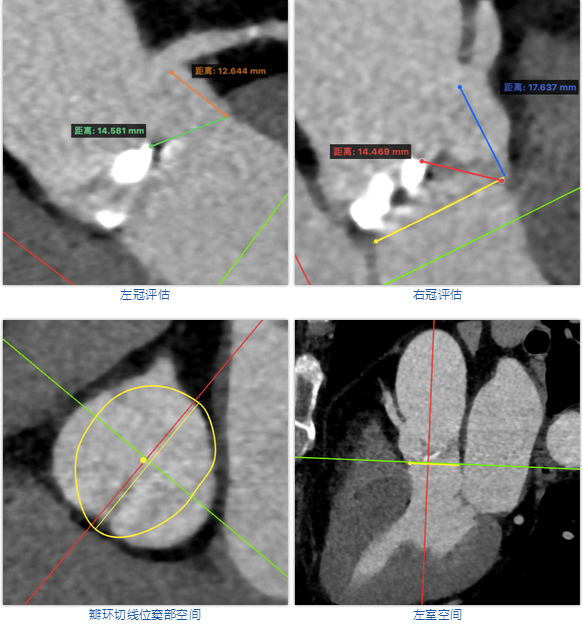

术者采用患者右侧主入路,顺利完成导丝和猪尾跨瓣等准备工作。进Landerquist超硬导丝,采用25mm球囊进行预扩,仔细评估冠脉风险后,决定对冠脉采取保护措施。根据球囊扩张情况,术中决定使用金仕生物的ProStyle预装干瓣TAV32。打开包装后,很迅速的完成了瓣膜和系统植入前的准备。输送过程系统和瓣膜轻松过弓并顺利跨瓣;开始初步释放,然后快速起搏下释放,发现位置略高后进行回收,重新定位后最终成功完成释放。反复造影发现冠脉存在阻塞风险,武汉协和团队按照风险预案在左冠植入4.0*18mm支架进行保护。术后显示左右冠脉血液灌注通畅,术后超声测量峰值流速1.45m/s,峰值压差8mmHg,几乎无瓣周漏。入路闭合顺利,无心脏及血管并发症,手术成功。

| 球囊扩张 | 初步释放 |

| 再回收后释放,术中冠脉评估 | 系统撤出 |

| 支架植入 | 术后评估 |